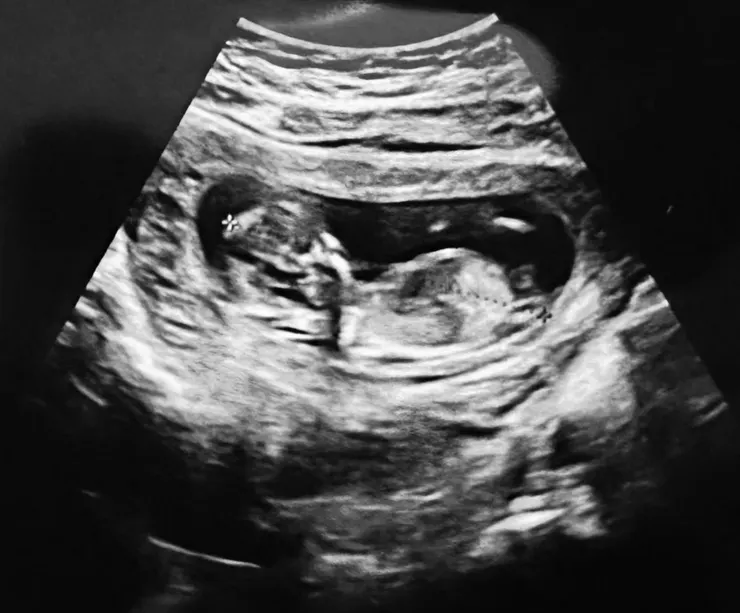

12w+6d又更大了